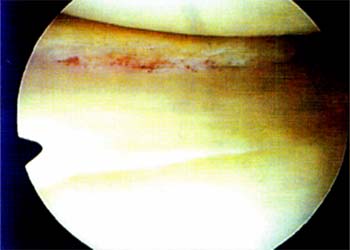

03_01_02_Foto3

Foto 3: Puntos en "U" en el plano vertical dados con hilo reabsorvible (Veril NQ 1)

03_01_02_Foto4

Foto 4: Second-look al mes de suturado el menisco interno (Foto 3) notese la cicatrización de los bordes con reabsorción parcial de los hilos.